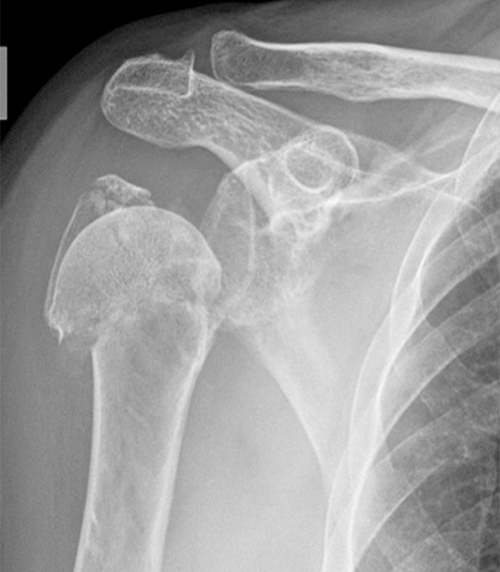

6. Κάταγμα-εξάρθρημα του ώμου

Στη διάρκεια ενός πεσίματος και βάζοντας το χέρι για να προστατευθούμε, αντί να συμβεί κάταγμα στον καρπό (βλέπε κάταγμα καρπού) συμβαίνει συχνά κάταγμα στον ώμο, δηλαδή στην κεφαλή του βραχιονίου οστού

Ο τραυματισμένος νοιώθει ισχυρό πόνο στον ώμο και αδυνατεί να κάνει τις φυσιολογικές κινήσεις του ώμου, δηλαδή άρση και στροφές

Το κυριότερο σύμπτωμα είναι ότι κρατάει το χέρι κολλημένο στο σώμα του.

Έλεγχος

Προσπαθώντας ν΄ ανοίξουμε το χέρι από τον καρπό, ο τραυματισμένος πονάει πολύ και μερικές φορές ακούει και «κριγμό» από το σπασμένο κόκκαλο. Άρα έχει κάταγμα.

Αντιμετώπιση

Όταν θεωρήσουμε με τον έλεγχο που κάνουμε ότι είναι κάταγμα, χρειάζεται ακινητοποίηση. Κρεμάμε το χέρι σ΄ ένα μαντήλι (προσέχουμε ο αγκώνας να βρίσκεται χαμηλότερα από το χέρι – δηλαδή το χέρι να βλέπει τον απέναντι μαστό) και σταθεροποιούμε το κρεμασμένο χέρι με μια ζώνη γύρω από τον θώρακα.

Πηγαίνουμε σε νοσοκομείο για ακτινογραφία.

Εάν το κάταγμα δεν έχει «φύγει» από τη θέση του, χρειάζεται να είναι κρεμασμένο για έξι εβδομάδες.

Κάνουμε όμως αιωρήσεις όπως στην περιαρθρίτιδα (1.000 την ημέρα) για να μην πάθει ο ώμος αγκύλωση.

Εάν το κάταγμα έχει «φύγει» χρειάζεται εγχείρηση. Σήμερα υπάρχουν μοντέρνοι τρόποι αντιμετώπισης των καταγμάτων του ώμου με πολύ μικρή τομή και άμεση κινητοποίηση του χεριού.